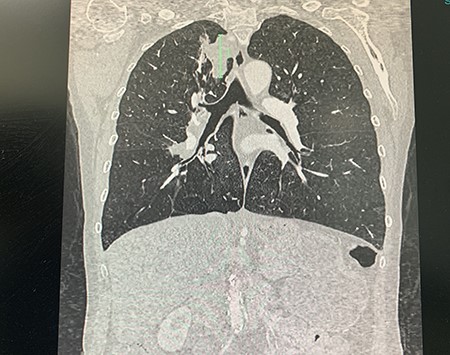

She presented to the operating theatre for excision with incidental dyspnoea and coryzal symptoms, and a pre-operative chest X-ray was arranged before any anaesthetic was administered, revealing a right upper lobe pulmonary mass partly obscured by the clavicle. She underwent excision of the cutaneous lesions, and respiratory physicians were consulted (Fig. 2). Urgent computed tomography (CT) chest was arranged, which revealed the diagnosis of lung malignancy, with a spiculating right apical mass measuring 48 × 30 × 29 mm, extending to the mediastinal pleura and in proximity to the oesophagus and posterolateral trachea with obliteration of the fat planes. There was also local hilar and paratracheal lymphadenopathy, measuring 30 × 29 × 20 mm in the right superior hilar region, 21 × 24 × 13 mm in the right inferolateral hilar region and a 36 × 14 mm pretracheal node (Figs 3 and 4). There were also background mild centrilobular emphysematous changes. There was no metastatic abdominal or pelvic disease.